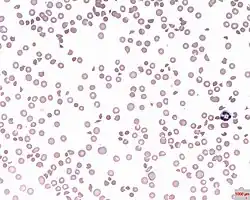

A photomicrograph of the blood showing thrombocytopenia

In hematology, thrombocytopenia is a condition characterized by abnormally low levels of platelets (also known as thrombocytes) in the blood.[2] Low levels of platelets in turn may lead to prolonged or excessive bleeding. It is the most common coagulation disorder among intensive care patients and is seen in a fifth of medical patients and a third of surgical patients.[3]

A normal human platelet count ranges from 150,000 to 450,000 platelets/microliter (μL) of blood.[4] Values outside this range do not necessarily indicate disease. One common definition of thrombocytopenia requiring emergency treatment is a platelet count below 50,000/μL.[5] Thrombocytopenia can be contrasted with the conditions associated with an abnormally high level of platelets in the blood – thrombocythemia (when the cause is unknown), and thrombocytosis (when the cause is known).[6][7]